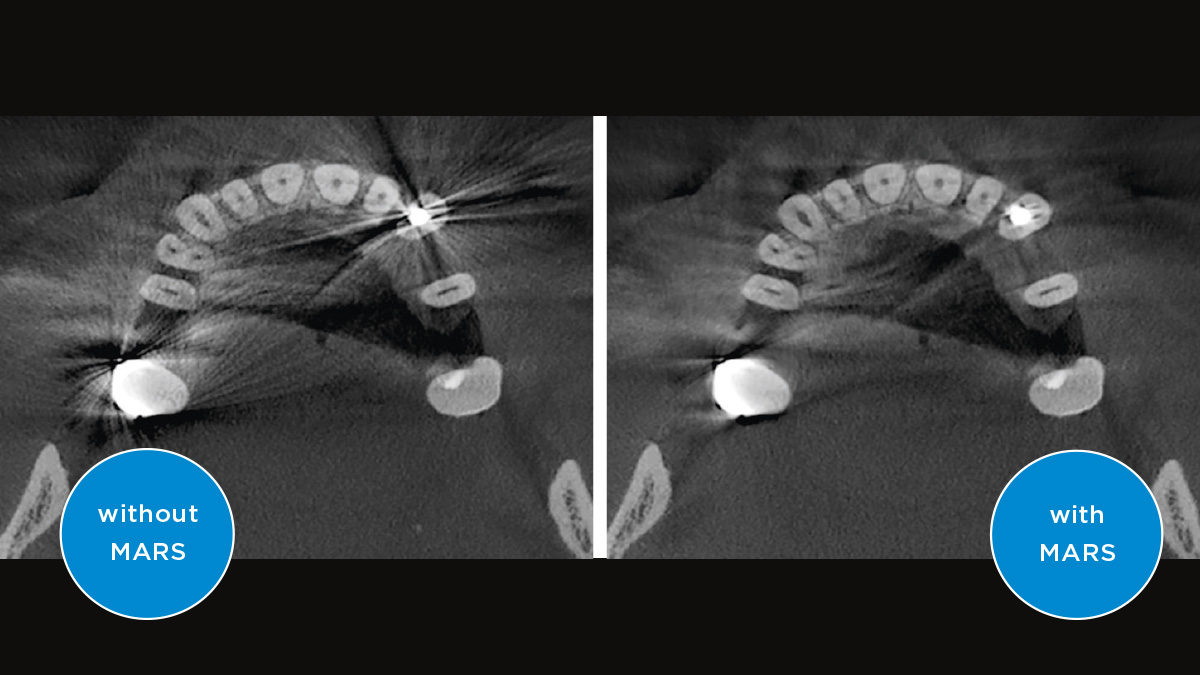

Met de 3D Intelligent Low Dose-modus krijgt u 3D-beelden in het dosisbereik van een 2D-röntgenfoto. In de HD-modus (maximaal 1400) worden afzonderlijke beelden vastgelegd tijdens een enkele rotatie en omgezet in een 3D-volume met maximaal 80 μm voor beelden in hoge resolutie met weinig verstoring.